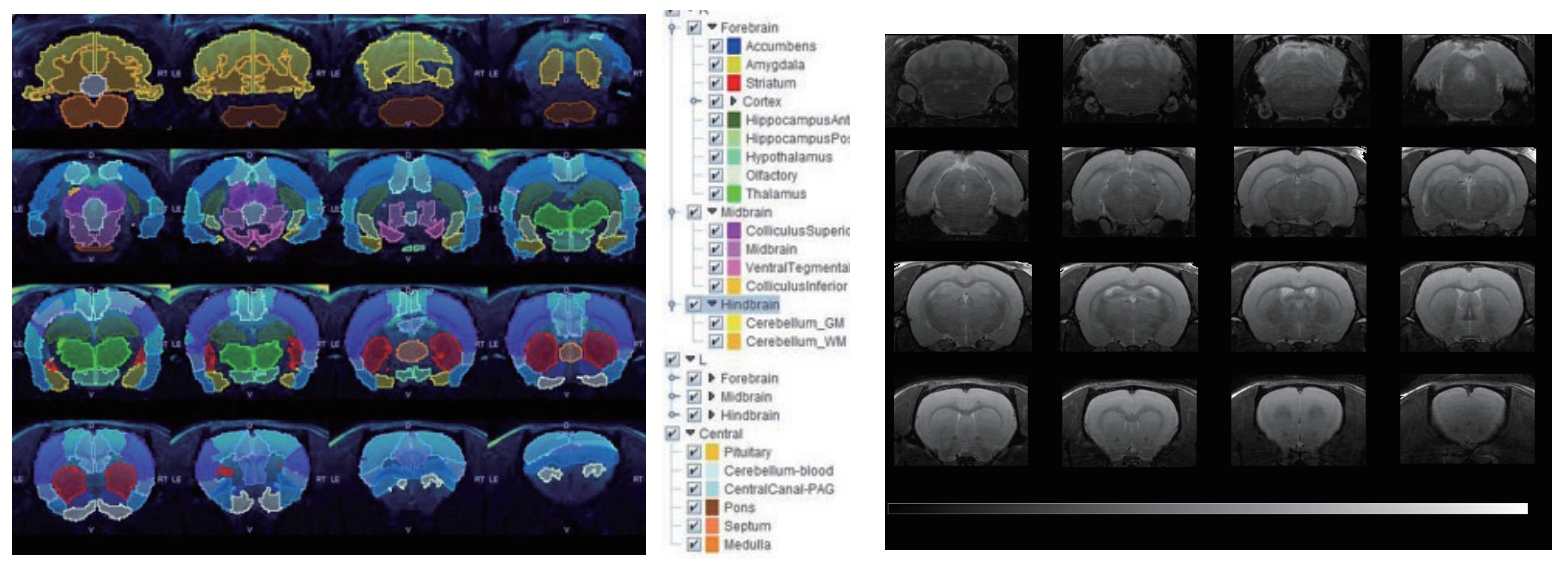

7T磁共振下大鼠腦部RARE影像,使用PMOD軟件分割。

大鼠腦部RARE影像.png